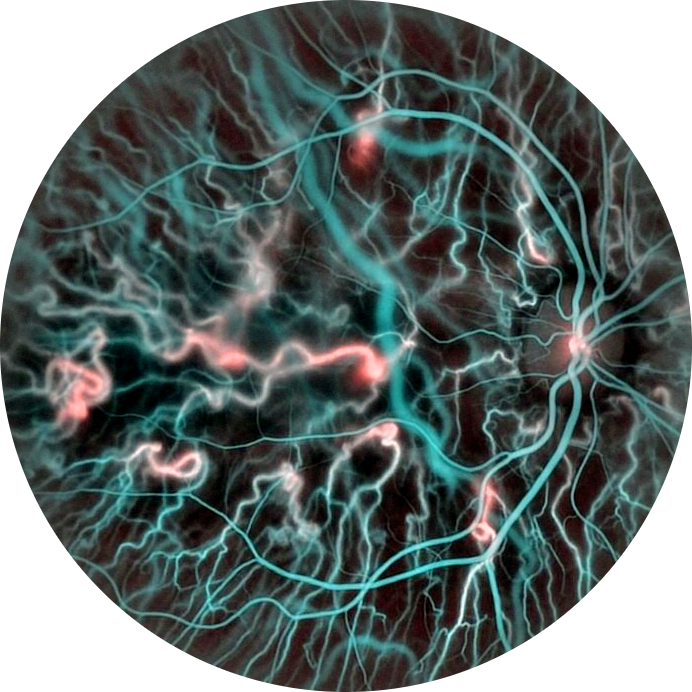

Quantitative retinal hemodynamics via Doppler holography

Quantitative blood flow analysis from Doppler holography data

flow velocity maps, arterio-venous pulsatility indices, blood volume rate, and vascular density metrics.